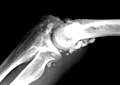

Gross/radiology

- Intraarticular calcifications.

- Diffuse involvement of the joint.

- +/-Loose bodies in the joint (AKA joint mice).

LOOSE BODIES, RIGHT ELBOW, REMOVAL: - FRAGMENTS OF BONE WITH CARTILAGE AND SYNOVIAL TISSUE COMPATIBLE WITH LOOSE BODIES.